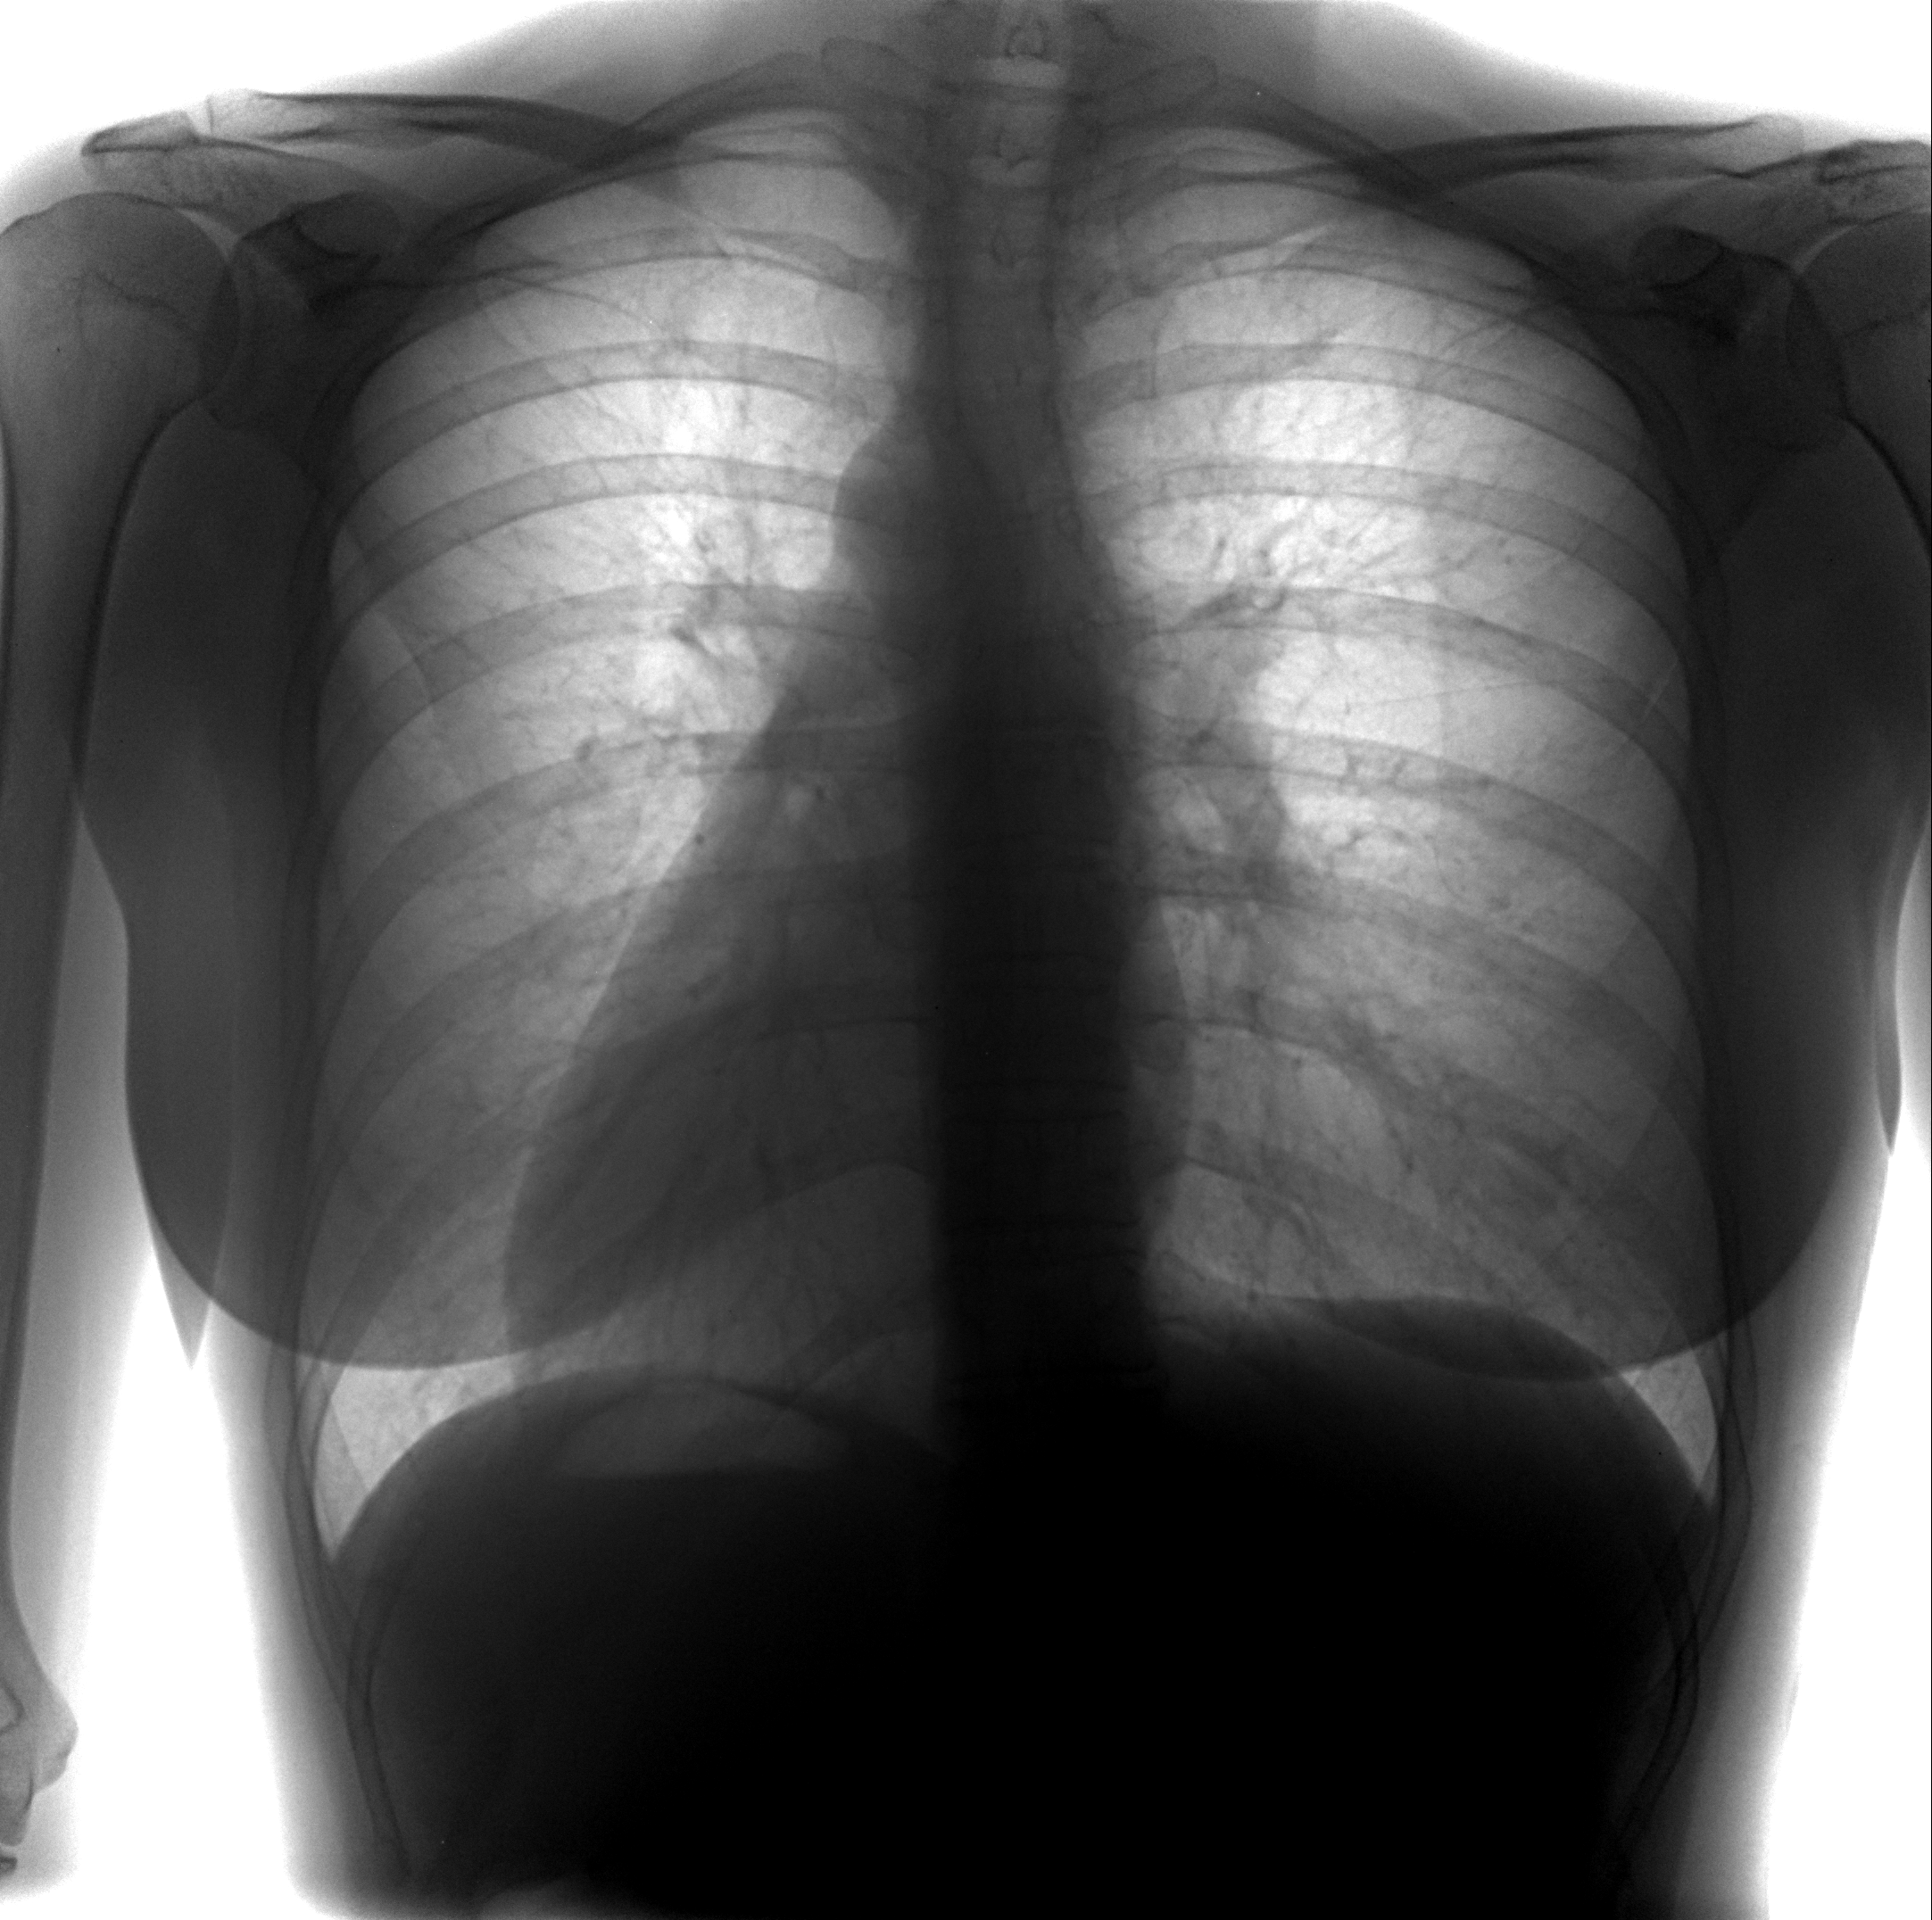

Снимок грудной клетки здорового ребенка: примеры и диагностика